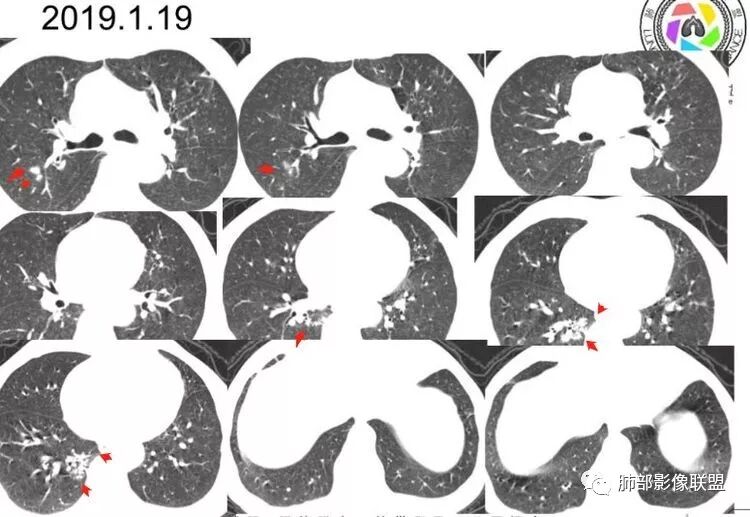

2019-1-19:空洞,纤维条索,树芽,实变;曲霉菌抗原阴性,1-3-B-D葡聚糖阴性;隐球菌抗原阴性;T-spot阳性;多次痰AFB,阴性;刷检,未见癌c。支气管镜(-),痰灌洗液培养(-);

老年男性,双肺多发簇状实变,周围点状卫星灶,边界较清(符合结核结节),左肺上叶薄壁空洞,空洞内壁光整,抗结核治疗后好转,首先考虑结核,左肺上叶病灶收缩力明显,有壁结节,需警惕恶性。

老年男性,间断咯血,气促咳嗽2年,左上肺薄壁不规则空洞,空洞壁有壁结节,壁薄,无内容物,形态不规则,较软。周围有胸膜牵拉,左肺上叶空洞下有斑片实变影,有卫星灶,双下肺游走性斑片结节影。血ige明显升高,尿有潜血,病程长,病灶此起彼伏,患者有手关节疼痛,考虑肉芽肿性血管炎,鉴别ntm。

患者老年男性,间断咯血、咳嗽2年,气促1年余。初查结核感染T细胞检测阳性,PPD阴性,痰查结核杆菌阴性,肿瘤标志物正常。胸部CT:左上肺薄壁不规则空洞,空洞壁光滑,形态不规则。周围有胸膜牵拉、纤维条索及点片结节卫星灶,双下肺游走性斑片结节影。予抗结核治疗病灶曾有改善。再次加重查血IGE明显升高,尿有潜血,且肺部病灶较前增多。结合其病程长,病灶此起彼伏,患者有手关节疼痛,综合考虑肉芽肿性血管炎合并结核可能性大,鉴别结核合并NTM、真菌及恶性病变可能。

左上叶薄壁空洞,可见长毛刺,邻近肺野可见播散灶,左下叶空洞周围亦可见渗出灶,炎性标志物不高,G十GM(一),空洞内无絲状物,抗TB治疗欠佳,综和考虑NTM可能性大

1.本例双肺多发病灶,边界较清楚的结节、树芽、薄壁异形空洞影……病灶符合典型继发性肺结核影像改变。